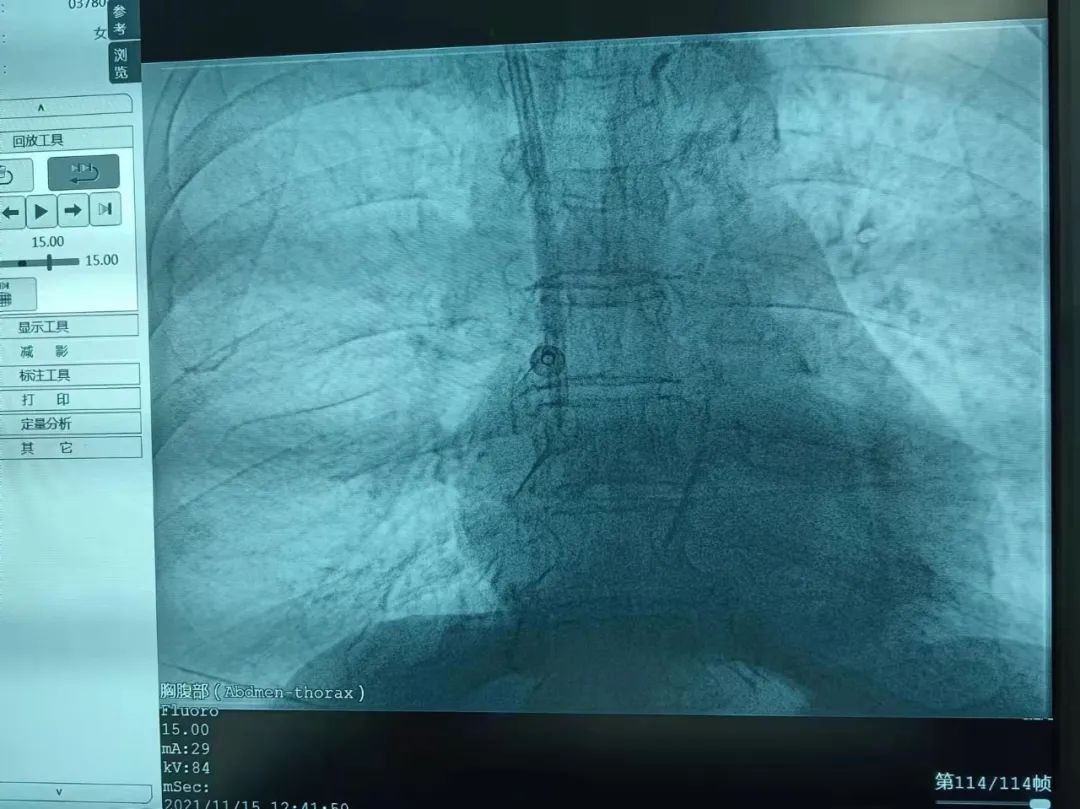

5月16日在山东大学齐鲁医院德州医院党委委员、副院长任洪波的带领下消化内科医疗团队运用消化内镜技术成功为一名胃底巨大肿物患者实施切除